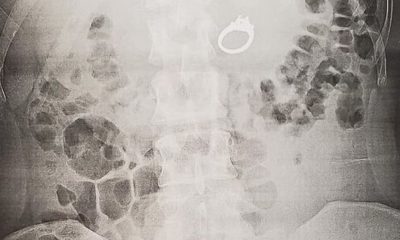

Идната невеста случајно го проголтала својот свршенички прстен за да го заштити додека сонувала ужасен кошмар. Џена Еванс од Сан Диего сонувала дека некој ја брка...